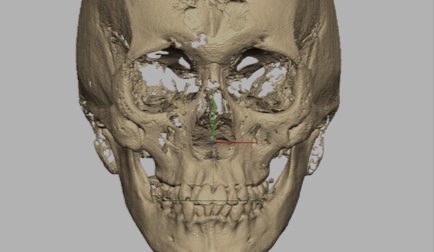

R2GATE® facial analysis: unique function that defines mid-facial plan, skeletal asymmetries, & esthetic problems

CBCT Reorientation

- Successful surgery requires accurate preoperative diagnosis & precise surgical planning

- CBCT analysis errors caused by slight patient movement can have significant impact on final surgical outcome

- Reorientation function corrects any patient position error during CBCT scan to provide best data for precise diagnosis